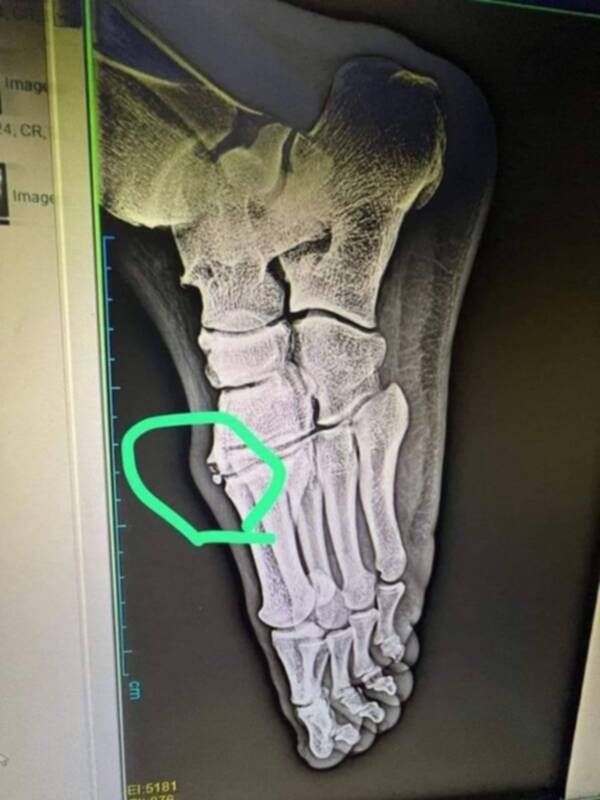

وقال المصدر لـ"كووورة": "أحمد فتوح تحامل على نفسه، وصمم على المشاركة أمام الأهلي رغم إصابته بكدمة في القدم.. وقد تفاقمت الإصابة حتى تعرض اللاعب لكسر في وجه القدم، وفقا للأشعة الطبية التي خضع لها صباح اليوم".

وأردف: "فتوح سيغيب عن الزمالك لمدة تتراوح بين أسبوعين وشهر، حيث يحتاج إلى راحة وبرنامج علاجي".